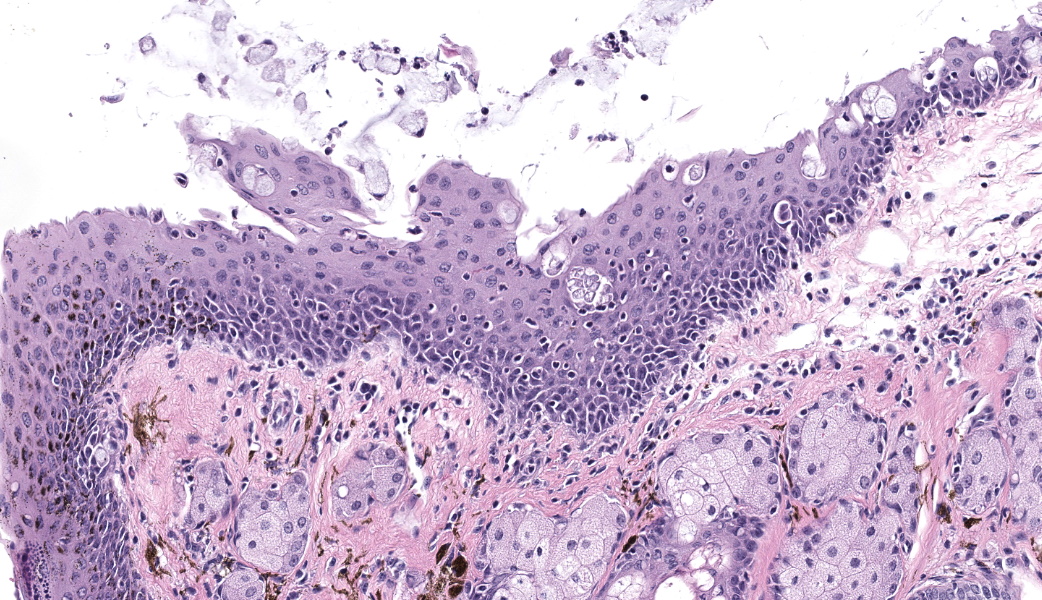

Bilaterally or unilaterally*, the eyelids contained locally extensive epidermal acanthosis and ortho to parakeratotic hyperkeratosis of varying severity. This was accompanied by epithelial erosion and mild serocellular crusting. There was mild to moderate mixed neutrophilic to lymphocytic inflammation within the conjunctiva and eyelid sebaceous glands (Meibomian glands). Focally there was occasional dilation and mild degeneration of Meibomian gland acini or ductules. The cornea, lens, iris, retina, optic nerve and other interior structures of the eyes were normal.

The Harderian gland was mildly enlarged (section plane-dependent) and glandular lumens contained occasional brown pigmented inspissated material (porphyrin secretions). Glandular epithelium lacked atypia and there was no compression or invasion as might be seen with adenoma or carcinoma.

- Eyelids: Blepharoconjunctivitis, neutrophilic, with epidermal acanthosis, erosions, and ortho to parakeratotic hyperkeratosis, unilateral to bilateral, moderate, chronic.

- Harderian gland: Hyperplasia with inspissated porphyrin secretions, bilateral, mild, chronic.